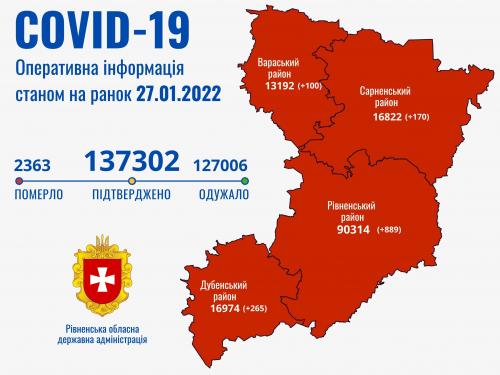

Коронавірус повертається: як стрімко зростає кількість хворих на Рівненщині (ВІДЕО)

Пів тисячі - у важкому стані, 9 жителів Рівненщини померли за добу від коронавірусу